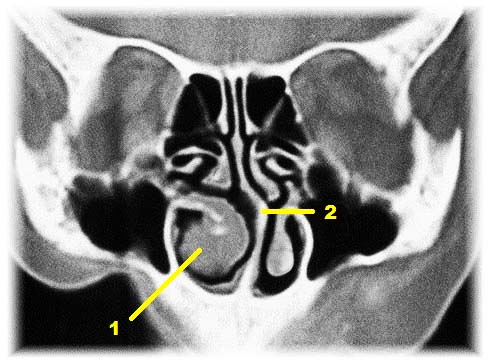

Prosta przegroda nosa

położona jest idealnie w linii pośrodkowej (1), natomiast jej

skrzywienia są bardzo różnorodne pod względem kształtu.

Z reguły jednak przeważa

skrzywienie w jedną stronę (2-5, 8-9) i co wydaje się logiczne to ta

strona nosa, w którą przegroda jest przesunięta ulegać powinna większemu

zwężeniu a co za tym idzie powinno się przez nią gorzej oddychać.

prostej. Kiedy spojrzy się na schemat, czy też zdjęcie z tomografii

komputerowej staje się to oczywiste. O ile drożność nosa po jednej

stronie ulegnie zapewne jakiejś poprawie to po stronie przeciwnej

dojdzie do znacznego pogorszenia przepływu powietrza, przez co osoba